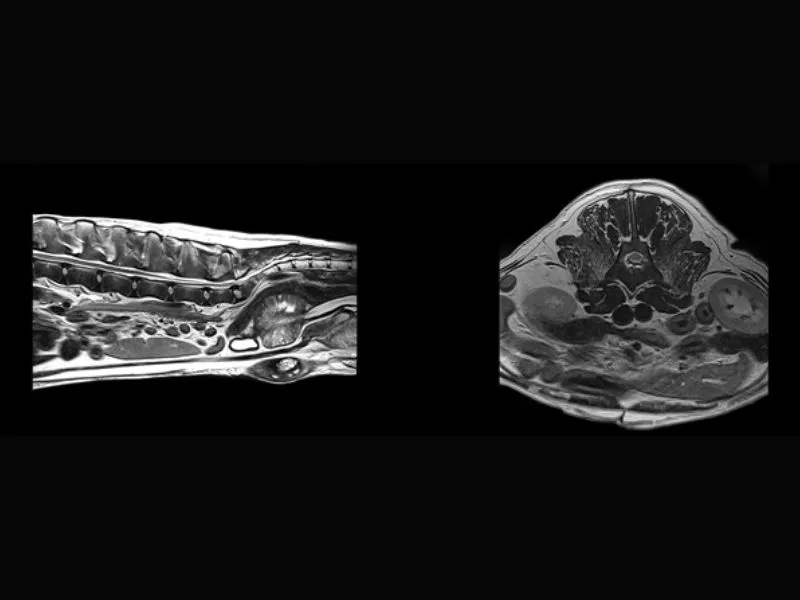

Supreme vet-mr – Multiple protruding discs in thoracolumbar, T1W and T2W slices